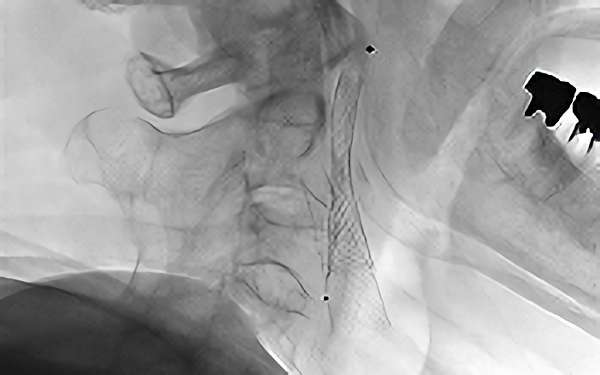

760

'20年2月12日

右内頚動脈狭窄症

80代

兵庫県の病院

手術写真

治療

前

中

後